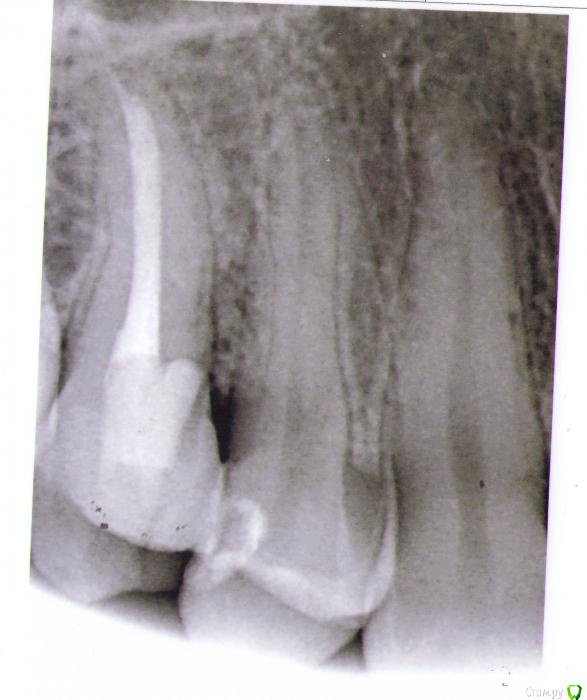

hichi Опубликовано 19 сентября, 2015 Поделиться Опубликовано 19 сентября, 2015 Добрый день. 6 месяцев назад проведено эндодонтическое лечение зуба. После этого через 1.5 - 2 недели острая боль от горячего. Подозревали дополнительный канал, зуб еще раз вскрыли, но ничего не обнаружили, еще раз обработали тот же самый канал и поставили кальций на 2 недели. На сегодняшний день реакции на горячее нет, но острая боль при чистке нитью между 1.4 и 1.5. когда вводишь и выводишь нить через контактный пункт. Как только пройдешь контактный пункт боль сразу же проходит. Десна не болит. Карманов нет. Кариеса тоже нет. Пару месяцев назад частично заменили пломбы в районе этого контактного пункта, но ничего не изменилось. Прилагаю снимок через 6 мес. Оцените, пожалуйста, все ли в порядке? Спасибо. Ссылка на комментарий

red_butler Опубликовано 25 сентября, 2015 Поделиться Опубликовано 25 сентября, 2015 Выглядит все очень прилично. Ссылка на комментарий

hichi Опубликовано 25 ноября, 2015 Автор Поделиться Опубликовано 25 ноября, 2015 И снова здравствуйте! 1. Плюс к вышеперечисленным симптомам появилась боль при накусывании, но не всегда а только если что-то мелкое и жесткое типа крошки от сухаря или косточки попадает на зуб. И только в одной точке - где-то у основания бугров, 14 или 15 точно не могу определить. Как куснешь сразу резкая боль и инстинктивно сразу зубы разжимаешь, точно не успеваю отследить но кажется что 14-й.На 14-м пломба сделана около года назад, около полугода назад частично скорректирована в районе контакта 14 и 15, зуб живой.С 15-м ничего не изменилось, все тоже самое что и в сообщениях выше. 2. Почему-то не растет сосочек пострадавший при реставрации контакта 14 и 15 полгода назад. Контакт нормальный - точечный и плотный, нить щелкает, по снимку уровень кости тоже в норме и перфорации и трещины 15-го тоже вроде как нет. Что может быть? 3. В 15-м не слишком ли тонкая стенка в том месте где не совсем удачно искали каналы, не треснет ли зуб от нагрузки? Имеет ли смысл делать вкладку или коронку и если да то изкакого материала с учетом того что противоположные зубы абсолютно здоровые? И если делать вкладку это же надо зуб снова сверлить, толщина стенки там осталась 0,32 мм не будет ли перфорации? Спасибо. Ссылка на комментарий